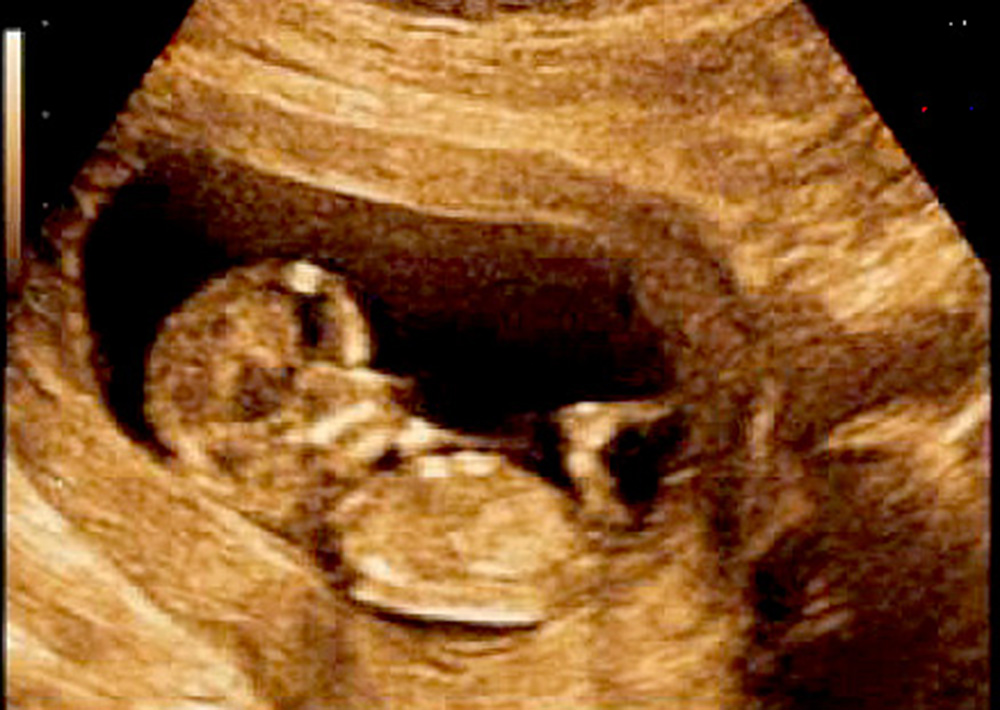

México, (Notimex).- Los cuidados prenatales durante el embarazo son fundamentales para evitar y detectar a tiempo posibles malformaciones en el bebé, ya que la mayoría de éstas ocurren en el primer trimestre de la gestación, señaló Agustín Guerrero Guillén, especialista en medicina materno fetal.